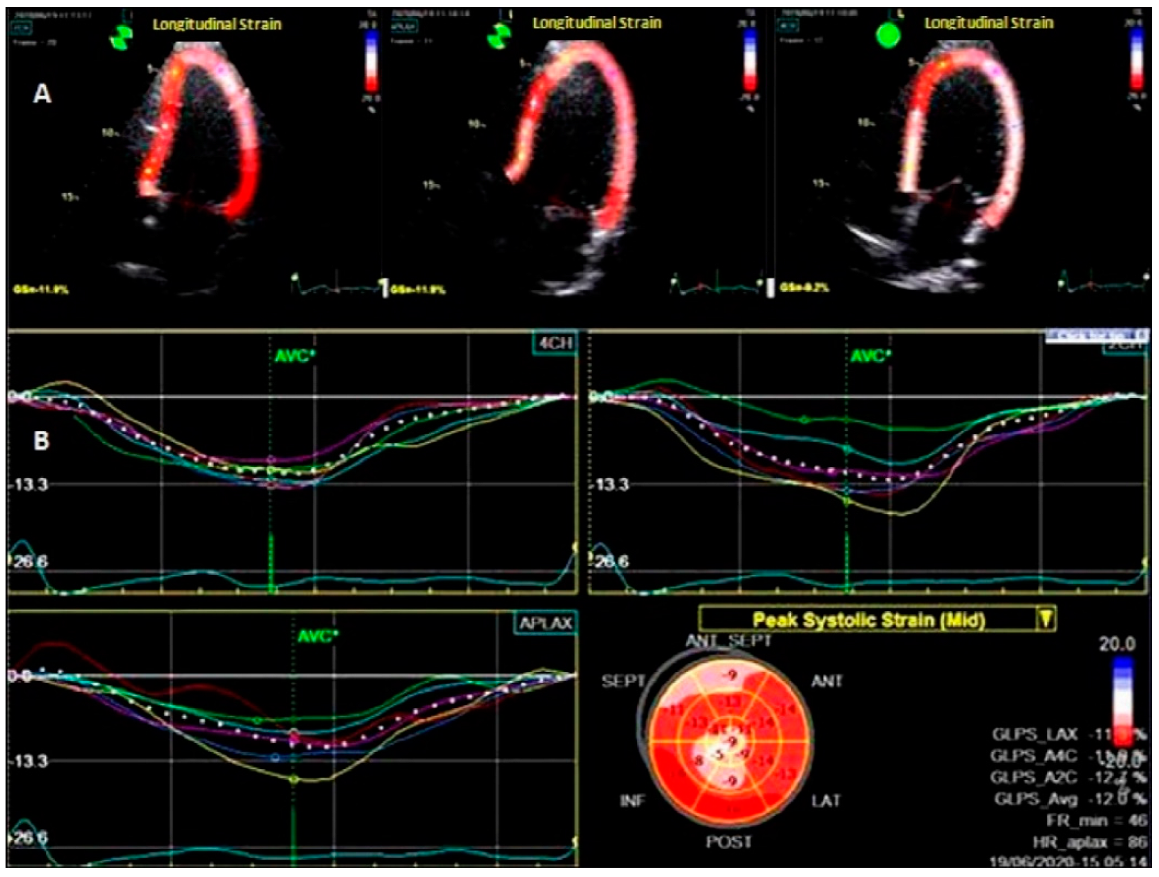

2.6.2. Two Dimensional-Speckle Tracking Echocardiography (2D-STE)

| ILS(%) | −13.1 (12.4, 14.00) | −12.3 (11.6, 12.8) | −12.9 (12.2, 13.8) | <0.0001 |

| ILSR (s−1) | −0.76 (0.70, 0.80) | −0.74 (0.69, 0.80) | −0.74 (0.69, 0.80) | 0.0004 |

| ILS (%) | 5.27 | 3.43–8.08 | <0.0001 |

| ILSR (s−1) | 0.04 | 0.01–0.13 | <0.0001 |

| ILS (%) | 5.77 | 2.90–11.46 | <0.0001 |

| ILSR (s−1) | 0.11 | 0.03–0.39 | 0.0005 |